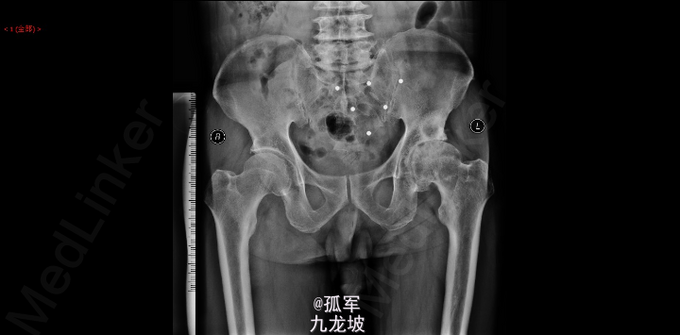

患者跛行步入病房 左侧:腹股沟中点压痛(+),大转子外侧叩击痛(+),左下肢轴向叩击痛(-)。 左髋:4字试验(+),Thomas征(-),滚动试验(+),Trendelenburg征(-)。 髋关节活动范围:左髋130°屈曲<->伸直0°,15°内收<->30°外展,15°伸直内旋<->20°伸直外旋。 骨盆正位片(2015-03):考虑左侧股骨头缺血坏死伴左髋关节退行性变,右侧股骨头缺血性坏死早期改变待排;

1.左侧Perthes病;2.左髋关节发育不良伴重度骨关节炎?3.腰椎间盘突出症 左侧人工全髋关节置换术 Link公司的TOP+LCU+陶瓷头